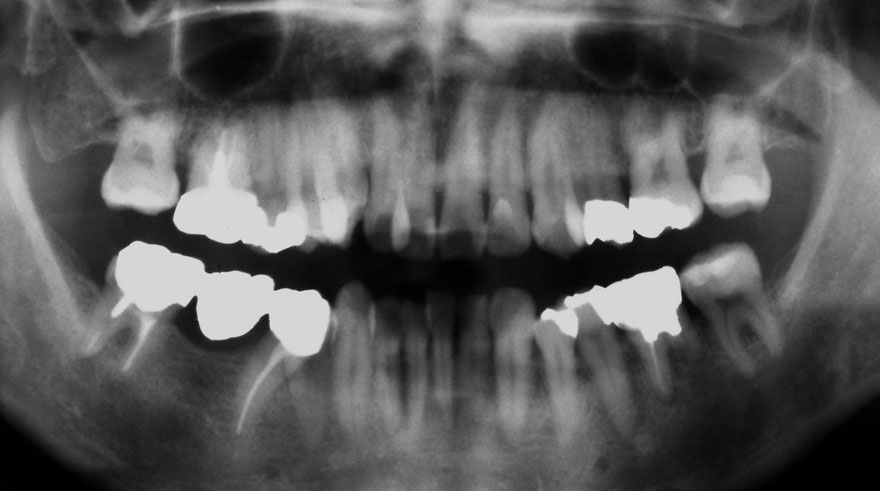

初診時 24歳 女性 平均歯槽骨喪失量:1.57mm

河田歯科医院

22年後 46歳

平均歯槽骨喪失量:1.72mm

22年間喪失量:-0.15mm

年間喪失速度:-0.007mm

(ケア頻度:1.35ヵ月ごと)